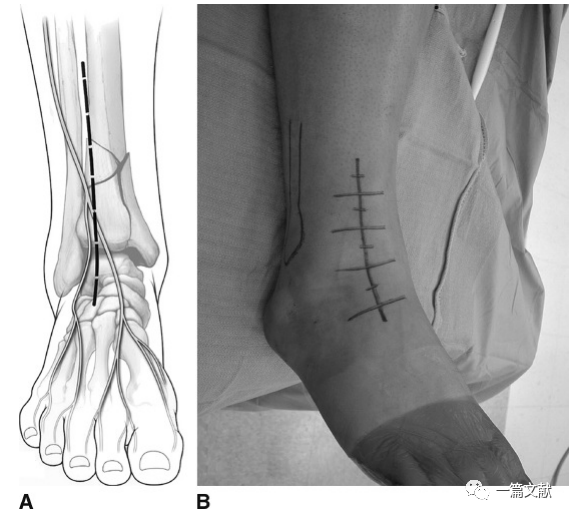

二,前外侧入路:于胫骨脊外侧约2-4cm处向远端纵行切开皮肤(约胫骨与腓骨中线),切口远端可达第四跖骨基地部,近端可达关节线以上7cm。如下图: